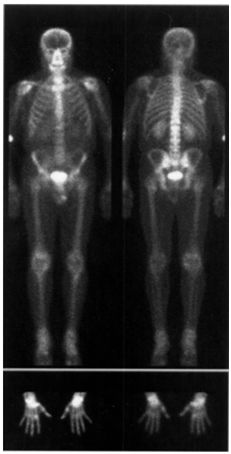

Laboratory tests showed only a mild leukocytosis 10.1´106/l, and the increased proportion of neutrophils (88.0%). Biopsy of the duodenal mucosa revealed the moderate atrophy of villi. In submucosal layer the separate groups of PAS-positive macrophages were again detected. Performed computed tomography of the abdomen showed no changes compared with the study from 12.12.2005. In the control of planar osteoscintigraphy (27.11.2007) (Figure 2), however, there were a positive dynamics. In comparison with the previous study there was no increased accumulation of the radiopharmaceutical in the left ankle. Accumulation in the right ankle, the left wrist joint, small joints of the hands, thoracic spine and both sacroiliac joints markedly decreased. At the same time moderately increased accumulation of the radiopharmaceutical in the right wrist joint. We calculated accumulation index (AI) as a ratio of the activity over the joint and the activity over the adjacent to the joint identical zone over bone. Data are presented in Table 1.

Figure 2 Planar osteoscintigraphy with TC-99m labeled sodium pyrophosphate (27-11-2007).